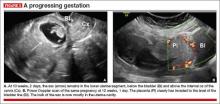

• close proximity of the gestational sac and the placenta to the anterior uterine surface within the scar or niche of the previous cesarean delivery (FIGURES 1B, 2A, and 2B)

• color flow signals between the posterior bladder wall and the gestation within the placenta (FIGURES 1B, 2B, and 3B)